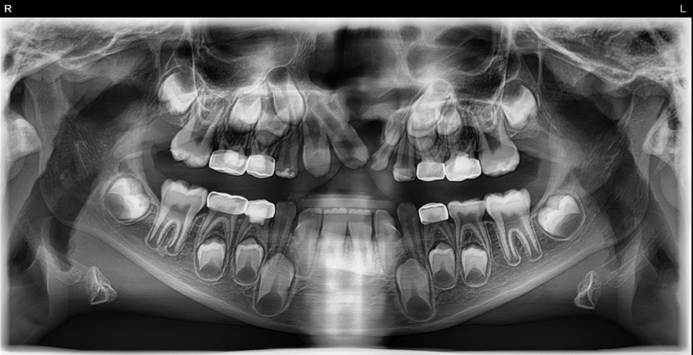

The patient record documented all operative events, materials used, activation schedules, and postoperative instructions. Parents were counseled on appliance care, oral hygiene during expansion, and the necessity of continuing follow‑up to time the alveolar bone graft relative to dental development (Figure 6).

Figure 6. Preoperative Orthopantomography (OPG) Showing Pulpotomized and Crowned Primary Molars; Peg-Shaped Tooth 62 Planned for Extraction